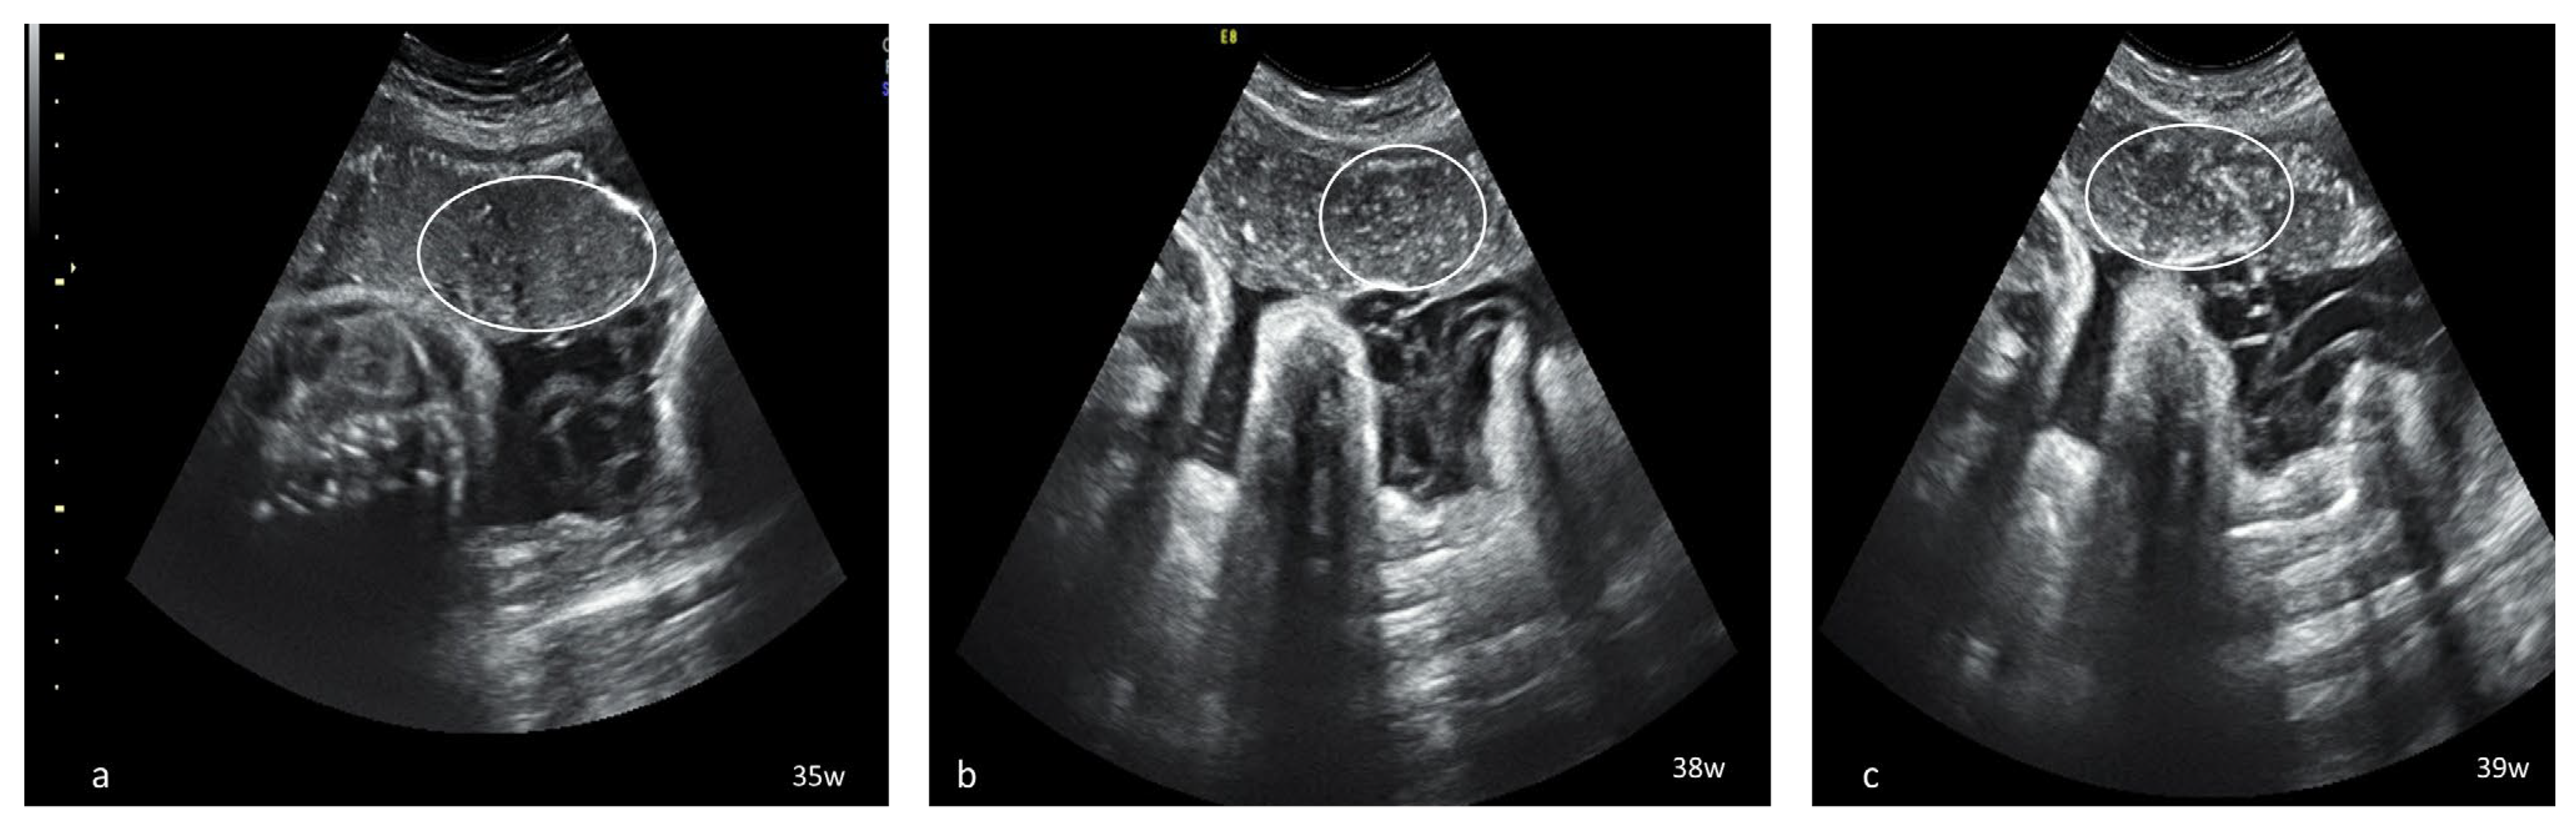

Dynamic evaluation of the placental morphology revealed what seems to be a particular pattern of placental remodeling starting from 30 WG towards term following SARS-CoV-2 infection during pregnancy. We noted the occurrence of dispersed hyperechoic foci, without posterior acoustic shadowing, scattered across the placenta, increasing in number and size with consecutive examinations, creating a “starry sky” appearance similar to the sonographic pattern described in acute hepatitis (Figure 1) [22]. Consequently, these foci conflate to form interlobular, chandelier-like, comma-shaped indentations. Later, lesions organize to form a consistent, chalky conglomerate along the entire basal plate, a “white line”, with bolded edges towards the chorionic plate forming white angles (Figure 2). Placental changes mimic the physiologic aging process but occur earlier in gestation; echo-dense foci are more widespread and organize in a short period to form the echoic white line.

Serial placental ultrasound images at 35 WG, 38 WG and 39 WG, of a nullipara with confirmed SARS-CoV-2 infection at 33 WG (a) hyperechoic foci scattered across the placental surface; (b,c) increasingly denser hyperechoic foci creating a “starry sky” placental pattern (circle).